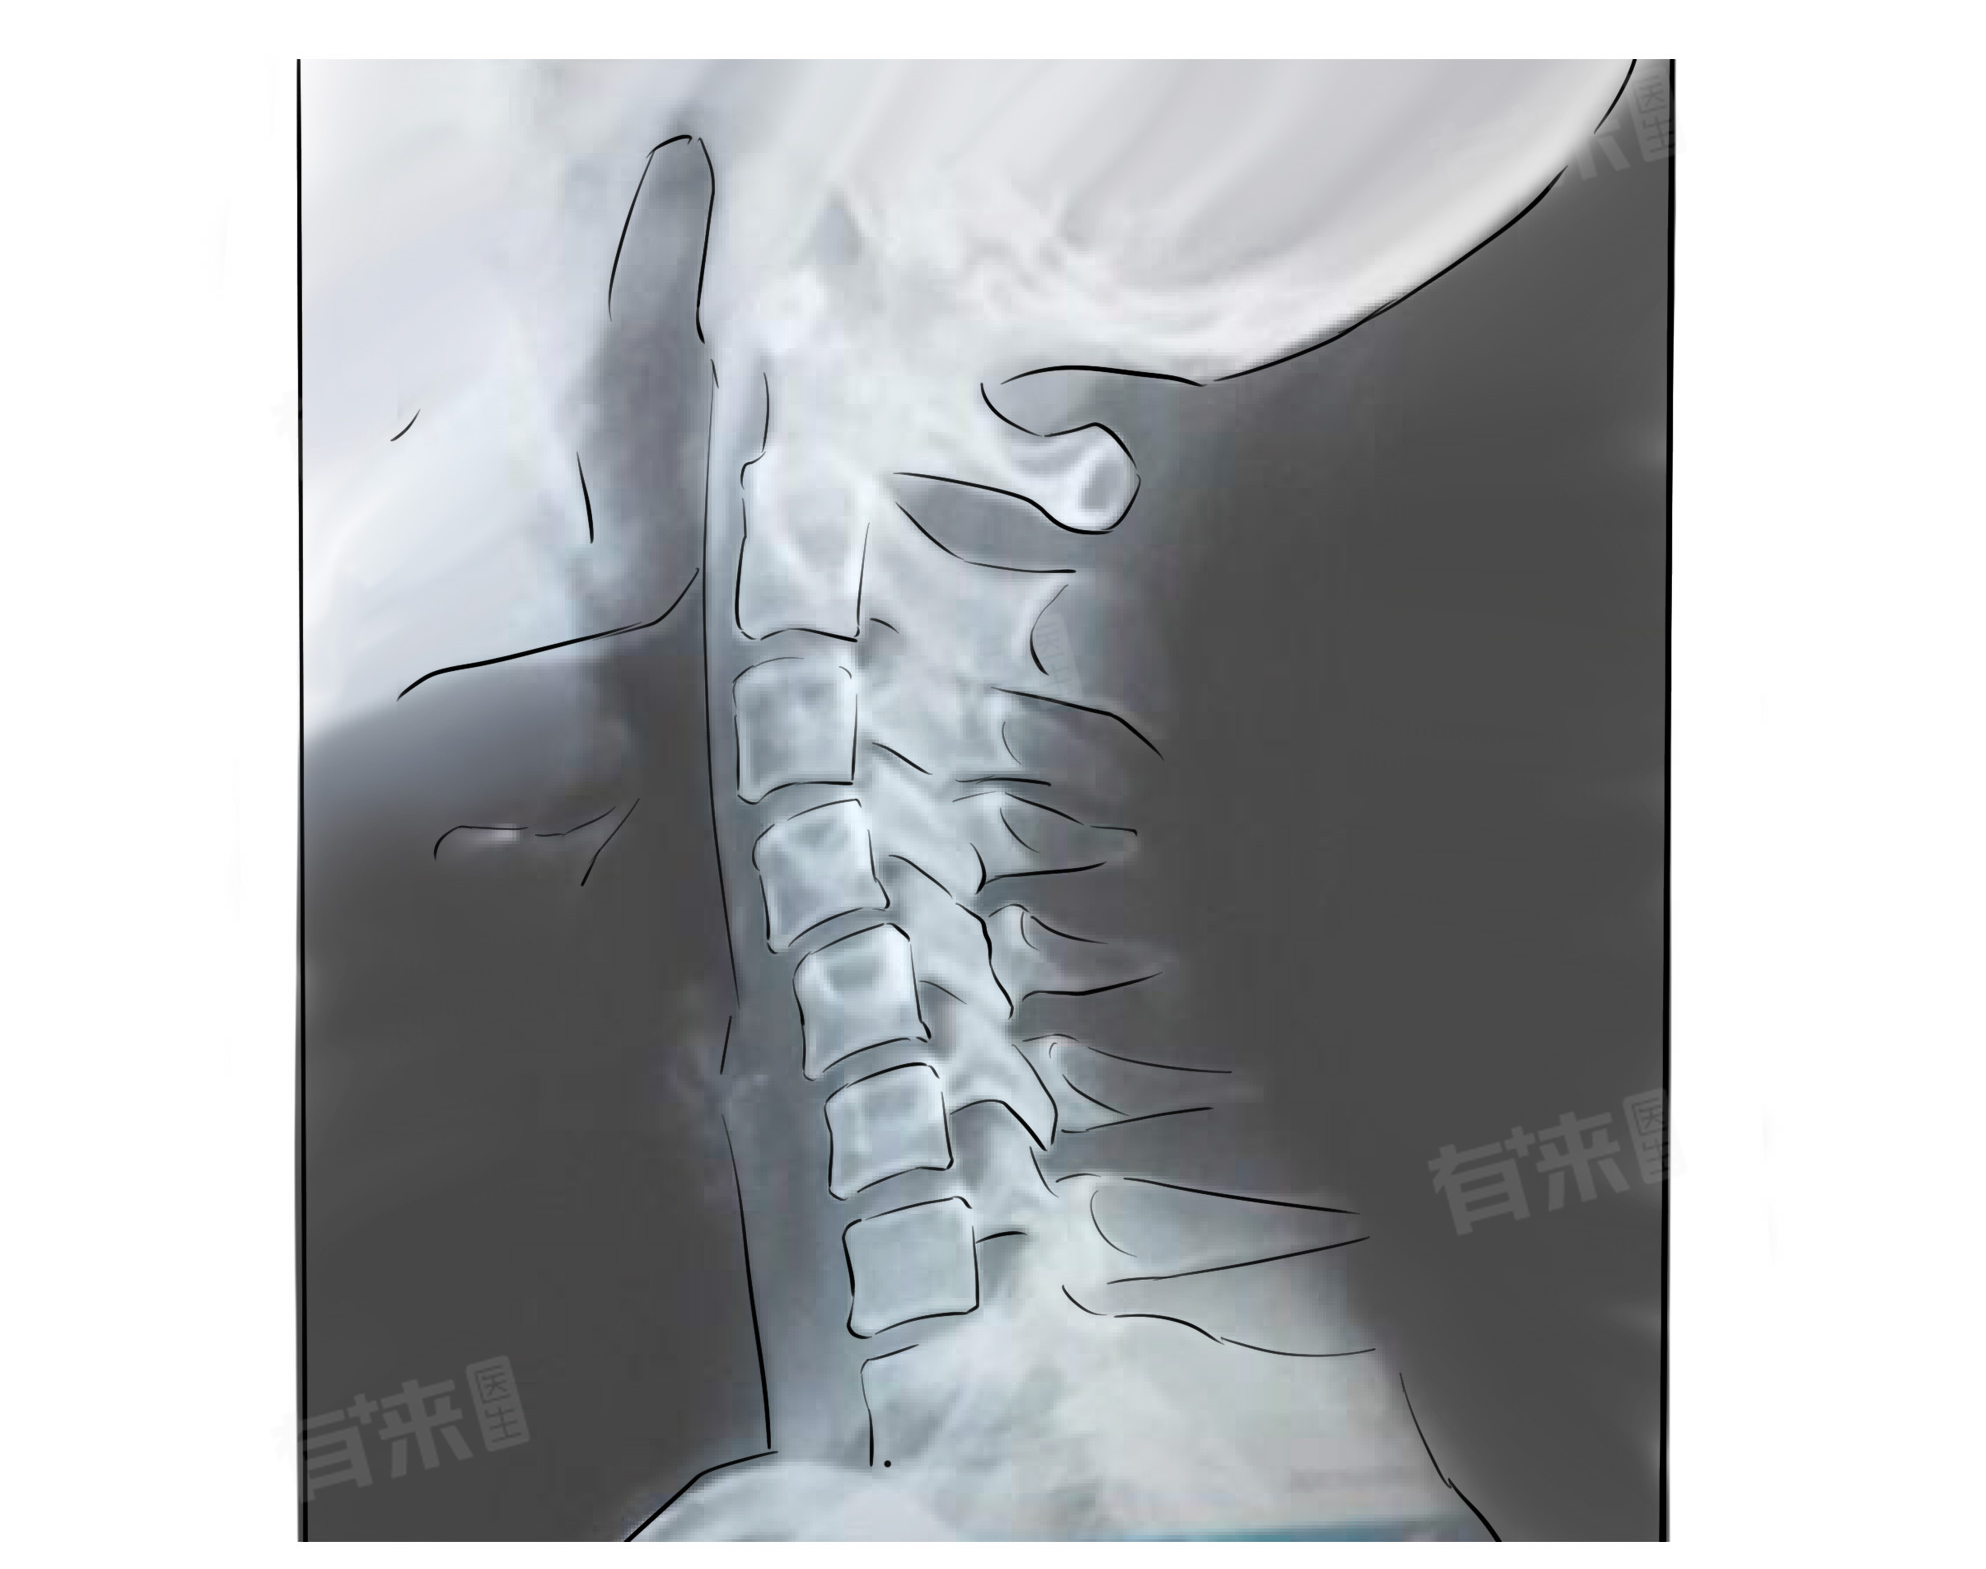

在检查颈椎时,CT和核磁共振都是常用的影像学诊断方法,但两者各有优缺点,适用于不同的检查需求。在选择检查方法时,应根据患者的具体情况和检查需求进行综合考虑,选择最适合的检查方法。

- 密度分辨率高:CT检查对密度的分辨率较高,能够清晰地显示颈椎的骨性结构,如椎体、椎弓、棘突等,对颈椎骨折、脱位、骨质增生等病变的显示效果较好。

- 软组织分辨率高:核磁共振检查对软组织的分辨率较高,能够清晰地显示颈椎的椎间盘、脊髓、神经根等结构,对颈椎病、颈椎管狭窄、颈椎外伤等病变的显示效果较好。

对于颈椎病患者,核磁共振检查是首选,因为它能够清晰地显示颈椎的椎间盘、脊髓和神经根等结构,有助于准确判断病变的性质和程度;对于颈椎骨折患者,CT检查是首选,因为它能够清晰地显示颈椎的骨性结构和骨折情况,为手术提供重要的参考信息。在选择检查方法时,还需要考虑患者的具体情况,如年龄、身体状况、检查需求等。对于孕妇、危重病人等特殊情况,需要在医生的指导下选择合适的检查方法。